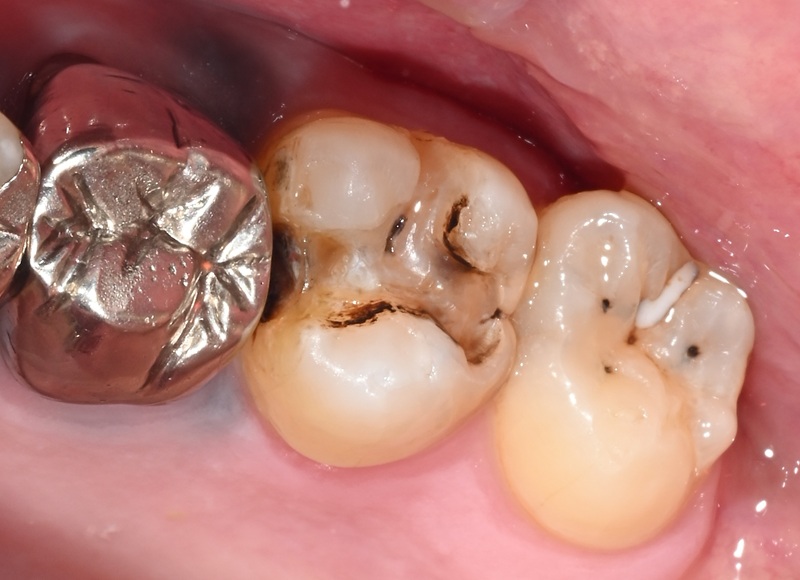

Case2

術前

術中

術後

| 治療名 | セラミックインレーによる虫歯の再治療症例 |

|---|---|

| 治療説明 |

過去に治療された銀歯が外れたとのことで来院されました。内部には古い接着剤の劣化と虫歯の再発が見られたため、しっかりと虫歯を除去し、セラミック製の詰め物(インレー)で再修復を行いました。 セラミックインレーは、天然歯に近い色調と自然な透明感を持っており、見た目が気になる部位にも適しています。 |

| 治療回数・期間 | 2回 |

| 副作用とリスク | ・保険診療の銀歯に比べて費用が高くなります。 ・治療直後は一時的に知覚過敏のような症状が出ることがありますが、ほとんどの場合は数日〜1週間程度で落ち着きます。 |

| 料金(税込) | 77,000円 |